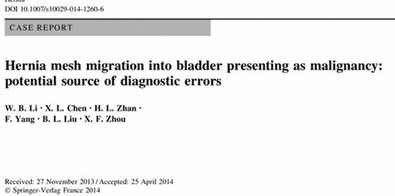

4. Siatka wrasta do sąsiednich narządów

Wszczepiona siatka powoduje reakcję organizmu – miejscowy stan zapalny. Nie jest to złe, gdyż dzięki temu siatka silnie przyrasta w miejscu wszczepienia. Niebezpieczeństwo powstaje, gdy siatka uwalnia się z miejsca jej umocowania oraz przemieszcza się w jamie brzusznej. Najczęściej siatka przedostaje się do pęcherza moczowego, ale może też dostać się do jelita cienkiego, grubego czy też innego narządu. Proces taki trwa wiele miesięcy lub lat. W tym czasie pacjent źle się czuje, ma stale bóle brzucha. Gdy siatka dostaje się do pęcherza objawem jest nawracające zapalenie. Gdy siatka przedostaje się do jelita – utrudnia przechodzenie treści jelitowej.